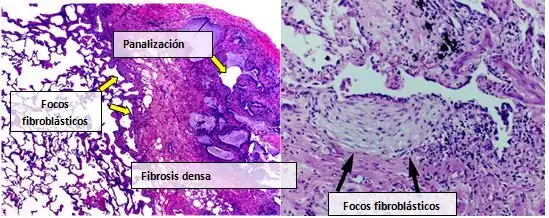

Normalmente, el tejido pulmonar de las personas afectadas por FPI muestra un patrón histopatológico de NIU característico y, por ello, es la contrapartida patológica de la FPI.[1][4] Aunque a menudo un diagnóstico patológico de NIU se corresponde con un diagnóstico clínico de FPI, en otras enfermedades y fibrosis de origen conocido (enfermedades reumáticas, por ejemplo), también puede apreciarse un patrón histológico de NIU.[1] Existen cuatro características clave de la NIU, incluida la fibrosis intersticial en un “patrón parcheado”, la cicatrización intersticial, los cambios por panalización y los focos de fibroblastos.

Los focos de fibroblastos son acumulaciones densas de miofibroblastos y tejido cicatricial, que, junto con la panalización, son los hallazgos patológicos principales que permiten un diagnóstico de NIU.